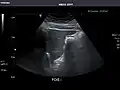

Renal ultrasonography

Ultrasound scan of a kidney (right side)

Ultrasonography of the kidneys is essential in the diagnosis and management of kidney-related diseases. The kidneys are easily examined, and most pathological changes in the kidneys are distinguishable with ultrasound.[7]